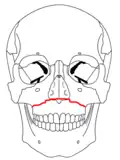

| Le Fort I fractures | |

At the beginning of the 20th century, René Le Fort mapped typical locations for facial fractures; these are now known as Le Fort I, II, and III fractures (right).[7] Le Fort I fractures, also called Guérin or horizontal maxillary fractures,[14] involve the maxilla, separating it from the palate.[15] Le Fort II fractures, also called pyramidal fractures of the maxilla,[16] cross the nasal bones and the orbital rim.[15] Le Fort III fractures, also called craniofacial disjunction and transverse facial fractures,[17] cross the front of the maxilla and involve the lacrimal bone, the lamina papyracea, and the orbital floor, and often involve the ethmoid bone,[15] are the most serious.[18] Le Fort fractures, which account for 10–20% of facial fractures, are often associated with other serious injuries.[15] Le Fort made his classifications based on work with cadaver skulls, and the classification system has been criticized as imprecise and simplistic since most midface fractures involve a combination of Le Fort fractures.[15] Although most facial fractures do not follow the patterns described by Le Fort precisely, the system is still used to categorize injuries.[5]